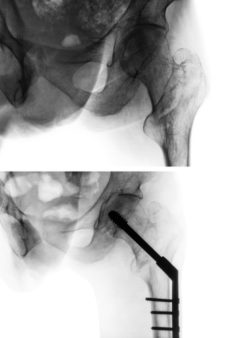

The DePuy Pinnacle hip implant lawsuit alleges that the plaintiff sustained unexpected injuries as a result of receiving a hip implant that was supposed to help her heal. Unfortunately, alleges the plaintiff, thousands of individuals have been affected negatively by the DePuy Pinnacle hip implant.

Shortly after the DePuy Pinnacle hip implant became available for patient use in 2002, DePuy began receiving adverse event reports of serious pain and problems alleges the plaintiff. Hundreds of similar complaints were lodged prior to the most recent DePuy Pinnacle hip implant lawsuit. The plaintiff in this particular DePuy Pinnacle hip implant lawsuit received her Pinnacle hip implant in March of 2008.

The plaintiff argues that DePuy was completely aware that the Pinnacle hip was defective and that numerous patients had already been seriously injured by that defect. The lawsuit alleges that the company should have used the hundreds of adverse event reports filed by previous patients to recall and stop selling the defective implant because it was clear it had catastrophically failed in numerous other cases. By the end of 2009, more than 750 reports have been received from patients who had that implant, points out the DePuy Pinnacle hip implant lawsuit.

Whether the hip implant became dislocated, revision surgery was required, or whether pain developed within the patient directly, a lawsuit is one of the ways a victim can recover compensation to move on and get medical support. Failure of the device or by the manufacturer to issue a recall may be grounds for a lawsuit.